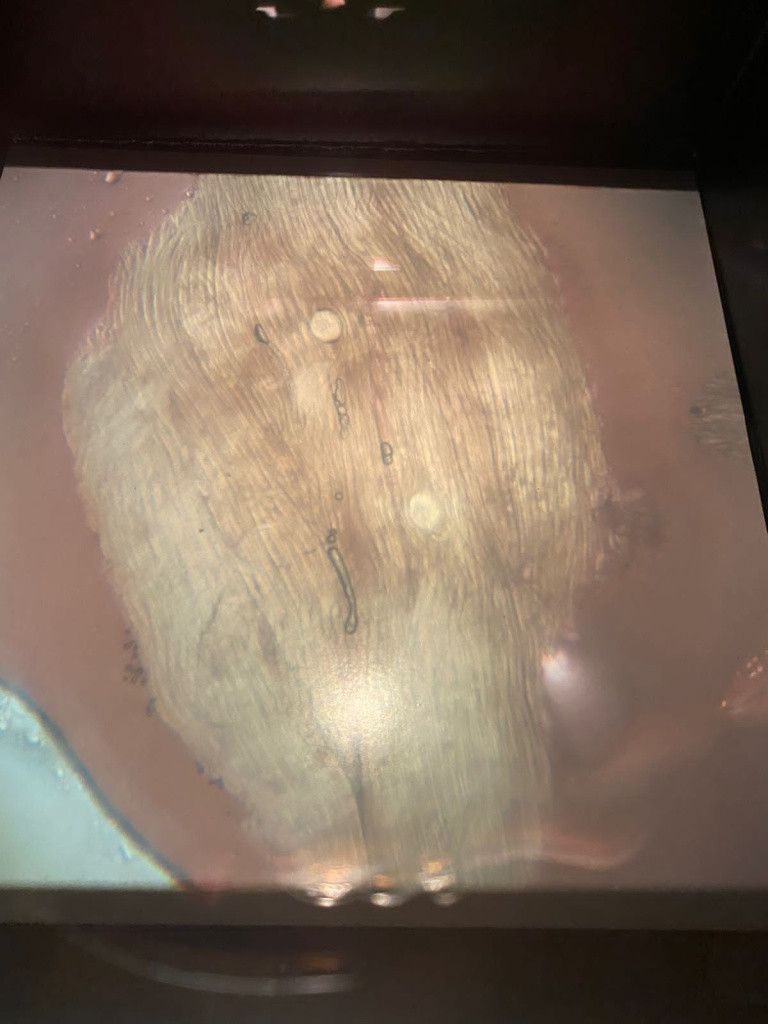

Государственная ветеринарная служба Мурманской области сообщает, что при проведении исследования туши медведя, добытого в Кольском районе, выявлены личинки трихинелл.

Трихинеллез - остро или хронически протекающая инвазионная болезнь всеядных, в том числе свиней, плотоядных животных, лошадей, а также грызунов. На личиночной стадии развития возбудитель находится в мышцах. Половозрелая форма возбудителя паразитирует в тонком отделе кишечника.

Фото: ГОБВУ «Мурманская областная станция по борьбе с болезнями животных»